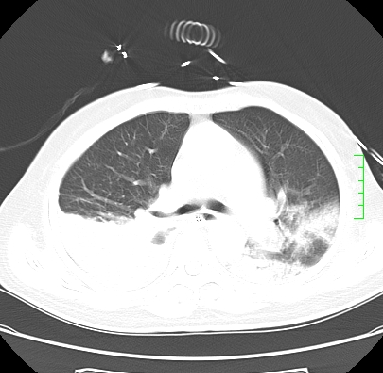

icu病人,几天都没明确诊断。m,76y,咳嗽、咳痰1周,伴气促,右胸痛入院,pe:t38.3c p135 r25 bp135/85。双肺可闻及大量湿罗音,心、腹未见明显异常。诊断:1心衰?2肺部感染?3冠心病?

11号ct

双肺感染性病变,下叶膨胀不全,胸水,左室大。

1)两肺感染性病变(右肺下叶肺脓肿可能)。2)双侧胸腔积液,以右侧为甚。

混合型肺水肿合并感染,肺膨胀不全,胸膜肥厚粘连包裹,同时肺内有陈旧性病灶。注意复查

考虑双肺感染、右肺下叶肺脓肿伴双侧胸腔积液。

ards,肺感染性病变,右下叶实变,双侧胸腔积液,右侧为著,叶间胸膜积液,右上肺陈旧性tb纤维灶,左室大。

考虑双肺感染、右肺下叶肺脓肿伴双侧胸腔积液,肺水肿。

考虑:双肺感染、右肺下叶肺脓肿,双侧胸腔积液,肺水肿.请结合临床.